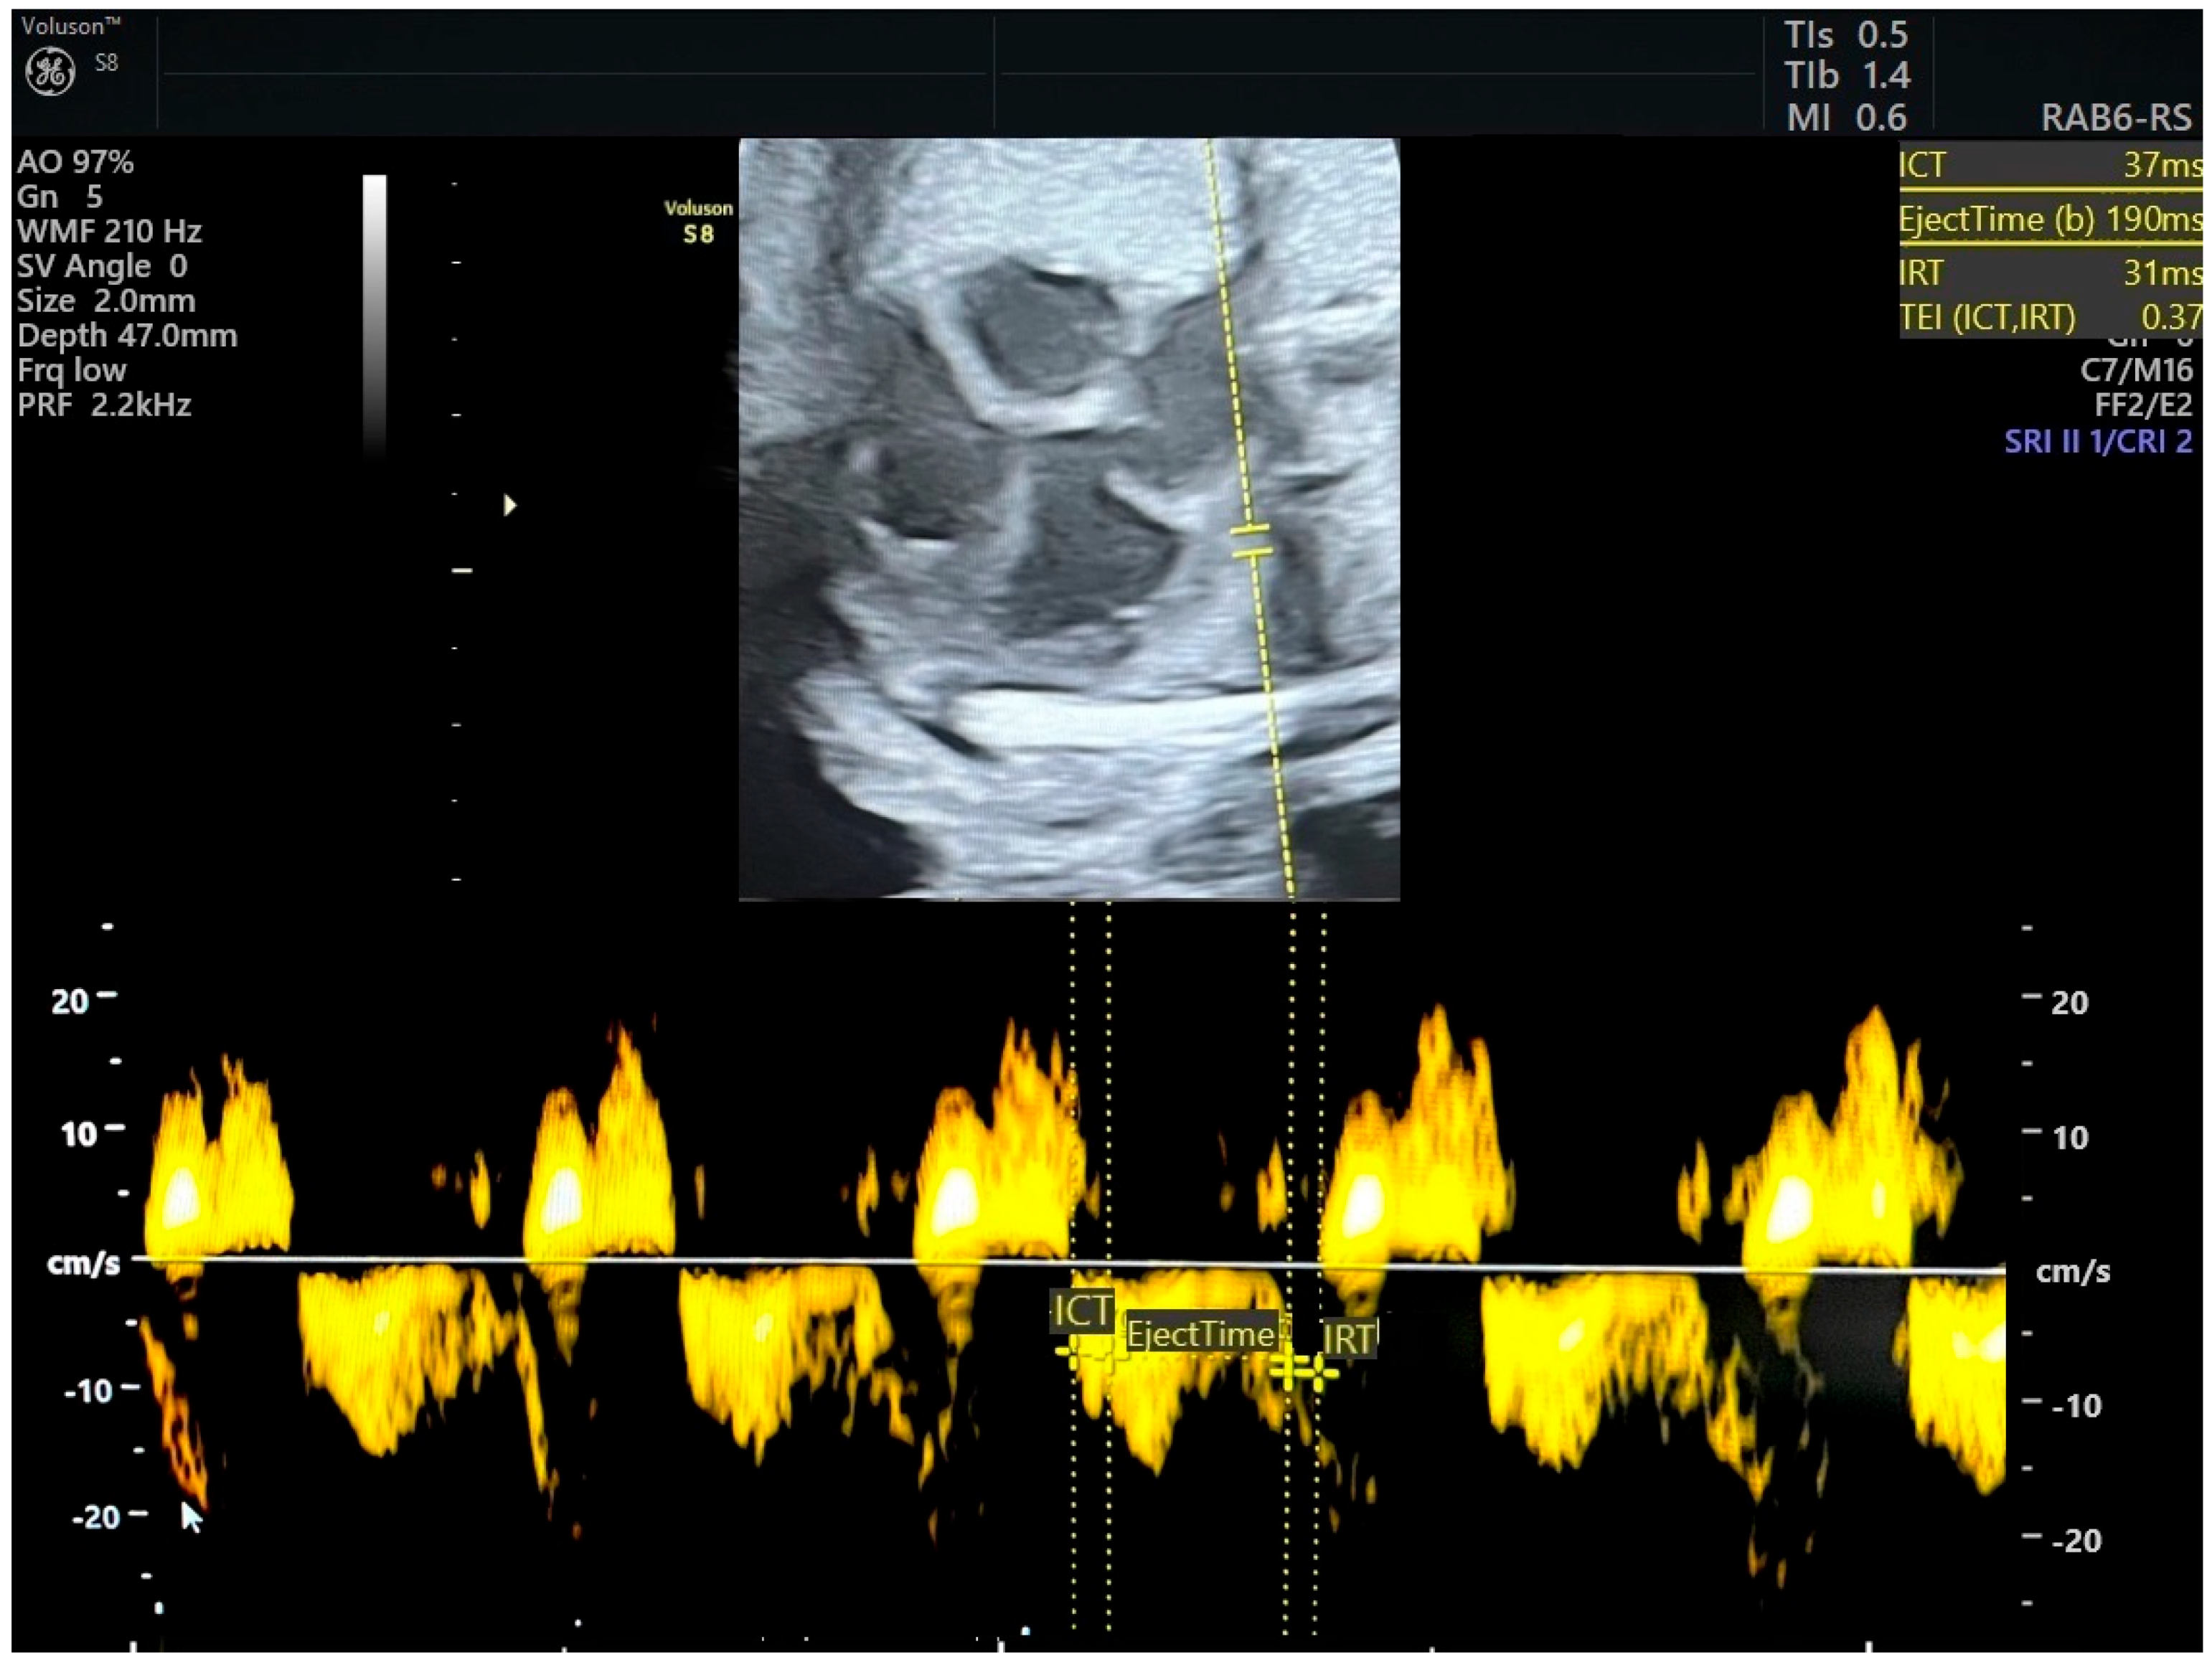

| RMPI TDI Values: Average 0.36 (0.28–0.44). Normal RMPI cut-off: 0.47 and below. | RMPI TDI Values:

| Timing: MPI alters before AoI and DV by 26, 12, and 5 days before delivery, respectively, which means that diastolic dysfunction occur prior to hypoxia. | Timing: MPI becomes altered before AoI and DV flow, which means that diastolic dysfunction occurs prior to hypoxia. |

Cardiac Impairment:

| Cardiac Impairment: